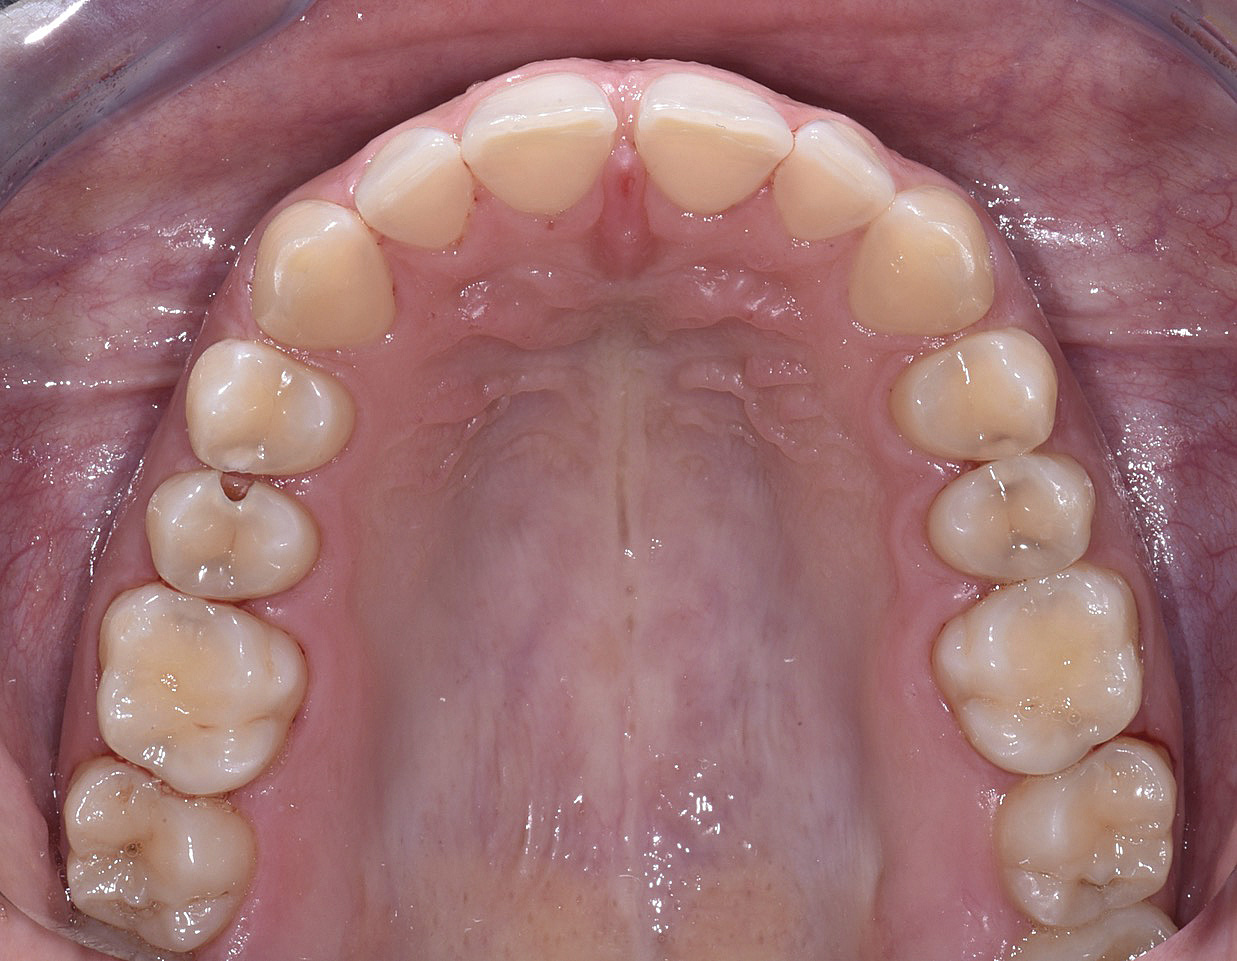

PREMESSA: in seguito all’estrazione dell’incisivo laterale superiore di destra, resasi necessaria per cause batteriche, si decide di affrontare il caso con il posizionamento di un impianto in sostituzione dell’elemento mancante dopo guarigione del sito infetto. Con tecniche rigenerative sia dei tessuti ossei mancanti a causa dell’infezione pregressa, sia dei tessuti gengivali che appaiono inizialmente troppo spostati in alto, si ripristina una corretta morfologia delle parabole (contorni) gengivali e delle papille interdentali (triangoli di gengiva tra due denti vicini).

Vengono utilizzati 2 tipi di provvisori: il primo, cementato ai denti vicini, viene utilizzato dal momento dell’estrazione del dente fino ad impianto osteointegrato (circa 6 mesi); il secondo, avvitato direttamente all’impianto, ha una funzione di prova estetica ma soprattutto di guida per la maturazione dei tessuti gengivali peri-implantari portandoli verso la maturazione completa prima di posizionare la corona finale in disilicato di litio.